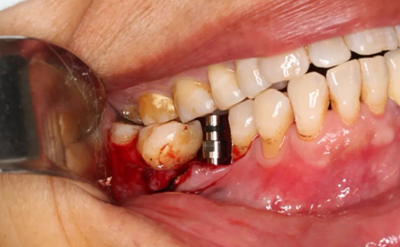

植入國產(chǎn)威高(WEGO)5.0×11mm種植體,檢查種植體位于理想軸位。

(攝于2017年4月14日)

取下攜帶體,旋入封閉螺絲,潛入式愈合。

組織瓣復(fù)位,常規(guī)間斷縫合。